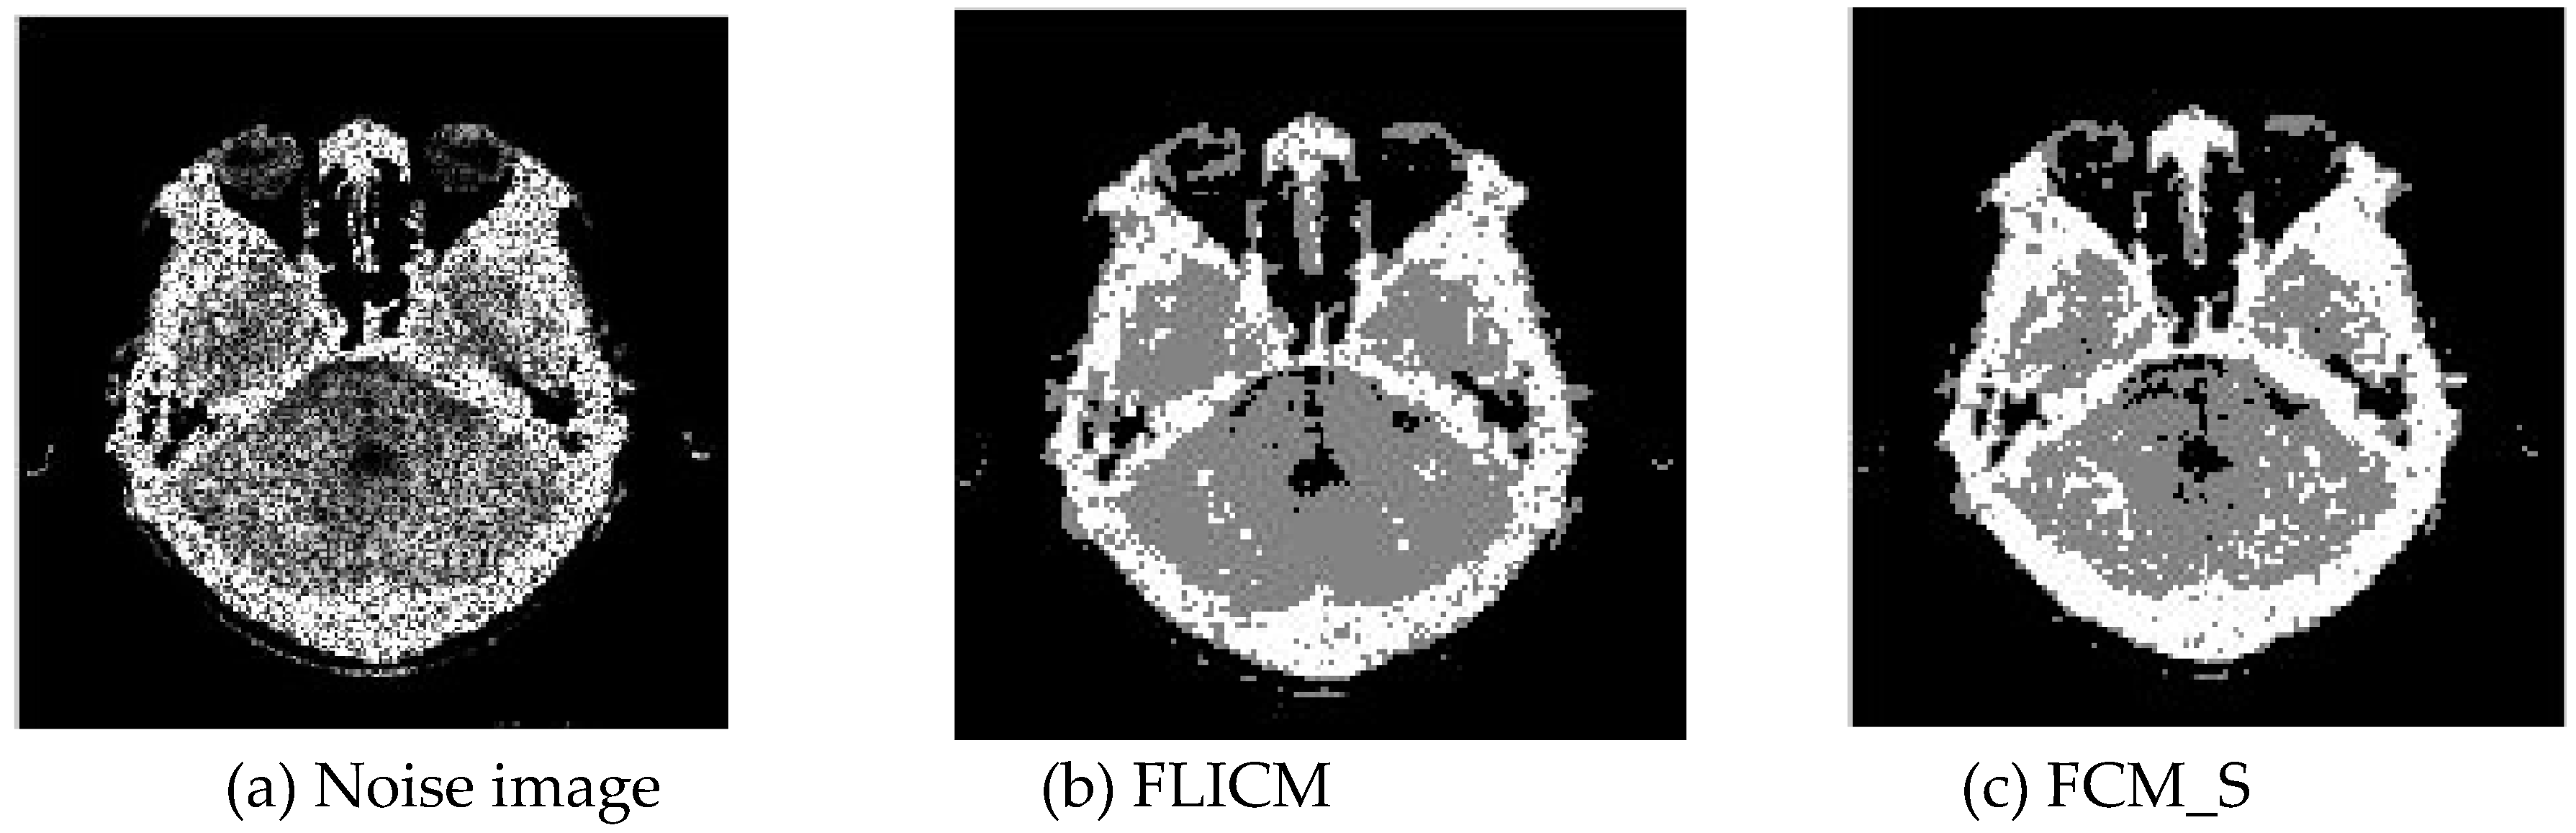

Gaussian noise was added to two remote sensing images with a mean value of 0 and mean variances of 57 and 80. Gaussian noise was added to images containing four artificial categories, brain CT (Computed Tomography) images, and camera images with a mean value of 0 and mean variances of 140 and 161. The number of clusters was set to 3, 4, 2, and 2. The results were compared using the results from the FLICM, FCM_S, LDMREFCM, and KWFLICM algorithms and the improved algorithm. The original image is shown in Figure 1, and the experimental results are shown in Figure 2, Figure 3, Figure 4 and Figure 5 (b–f). The error rate and PSNR of the segmentation results are shown in Table 1 and Table 2, and the iteration time and the number of iterations are shown in Table 3 [40,41].

3.1.2. Test Result

Comparing the segmentation results of the five algorithms in Figure 2, Figure 3, Figure 4 and Figure 5 for four images with different degrees of Gaussian noise interference, we can see that the segmentation results of the FCM_S, FLICM, and LDMREFCM algorithms still contained many noise points; the KWFLICM algorithm contained fewer noise points; while the improved algorithm has the fewest noise points. Table 1 shows that the improved algorithm had the highest signal-to-noise ratio compared with the other four algorithms, which shows that the improved algorithm had the strongest anti-Gaussian noise ability. Table 2 shows that the segmentation result of the improved algorithm was the smallest of all the algorithms, which shows that the segmentation result of the improved algorithm was closer to the ideal segmentation result and had a better segmentation performance. Comparing the PSNR and iteration time of each algorithm in Table 3, the average PSNR of the improved algorithm was 0.7 dB higher than that of the KWFLICM algorithm, and the average iteration time of the improved algorithm was 500 s less than that of the KWFLICM algorithm [42,43]. The iteration times of the FCM_S and FLICM algorithms were the lowest, but the difference between the improved algorithm results and the PSNR was 2–5 dB. The anti-noise ability of the FLCM and FCM_S method was poor. Combining the PSNR test results and the iteration time, the improved algorithm had a better anti-Gaussian noise segmentation performance.

Figure 4. Gaussian noise interfering with the brain slice image (a) and the segmentation results (bf).

Sensors 20 02391 g004